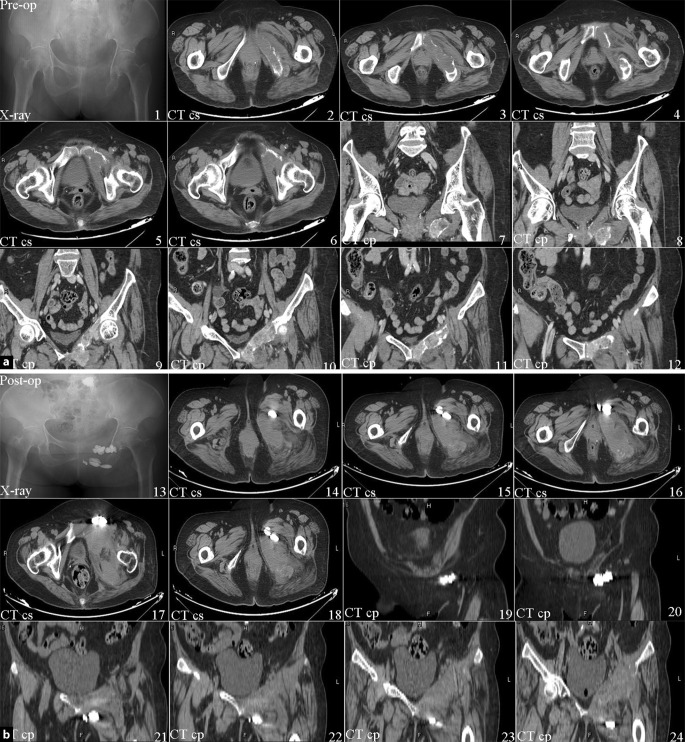

During surgery, the patient’s blood pressure, electrocardiogram pattern and pulse oximetry waveforms were all stable. Complications such as limb nerve injury, bleeding, embolism and infection did not occur during and after surgery. During the following 3 days, the patient was able to fall asleep without feeling pain. The VAS score decreased from preoperative 8 to postoperative 3. After 6 months the VAS was stable at 2. Details of the VAS are shown in Fig. 1. Preoperative and postoperative images are showed in Fig. 2.

Fig. 2.

a Pre-op preoperative, b post-op postoperative. The preop CT shows the bone surface was sufficiently intact. The postop CT shows the bone cement filled the metastatic lesion and extruded into the soft tissues. CT cs computed tomography cross-section, CT cp computed tomography coronal plane